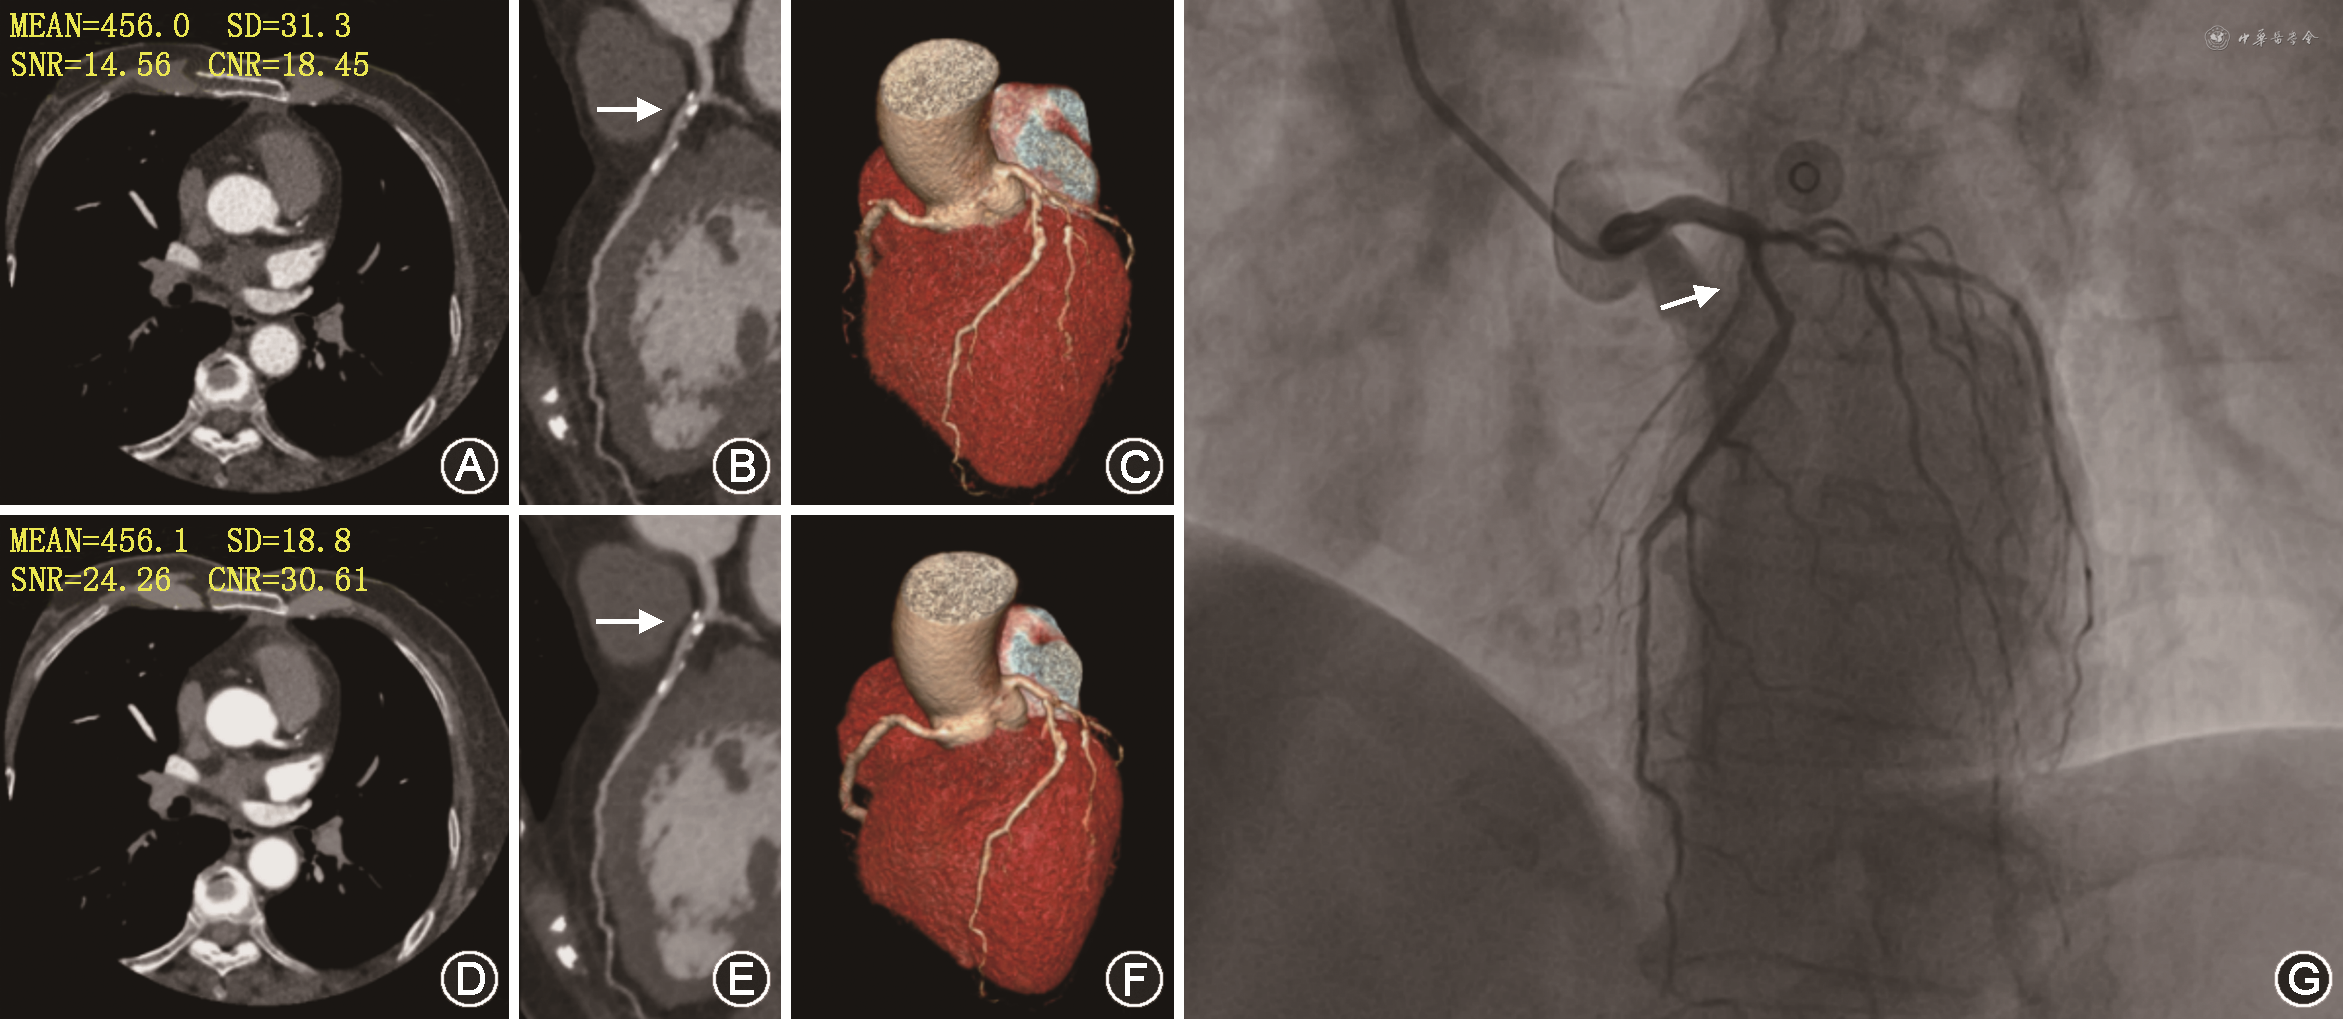

DLR图像噪声明显低于HIR图像(主动脉根部:18.12±3.66比24.19±5.71,P<0.001)。DLR图像的CNR和SNR均高于HIR图像(主动脉根部CNR:43.83±23.73比26.38±9.69,P<0.001,SNR:26.66±7.83比21.23±8.65,P<0.001)(图1)。

以病变为分析单位,DLR与HIR图像诊断钙化或混合斑块引起的≥50%面积狭窄的灵敏度、特异度、阳性预测值、阴性预测值和准确度分别为83.0%、84.2%、76.5%、88.9%、83.7%及85.1%、75.0%、67.8%、89.1%、78.9%。DLR图像诊断准确性优于HIR图像(83.7% 比78.9%,P<0.001)。与HIR相比,DLR图像上的假阳性病例由19例降低到12例,假阴性病例增加1例。DLR与HIR图像诊断钙化或混合斑块引起的≥50%直径狭窄的灵敏度、特异度、阳性预测值、阴性预测值和准确度分别为100.0%、77.4%、23.5%、100.0%、78.9%及100.0%、63.5%、16.0%、100.0%、65.9%。DLR图像诊断准确性优于HIR图像(78.9%比65.9%,P<0.001)。与HIR相比,DLR图像上假阳性病例由42例降低到26例,CCTA的假阳性病例减少38%(表3和图2)。

注:MEAN为平均CT值(单位:HU);SD为图像噪声;SNR为信噪比;CNR为对比噪声比